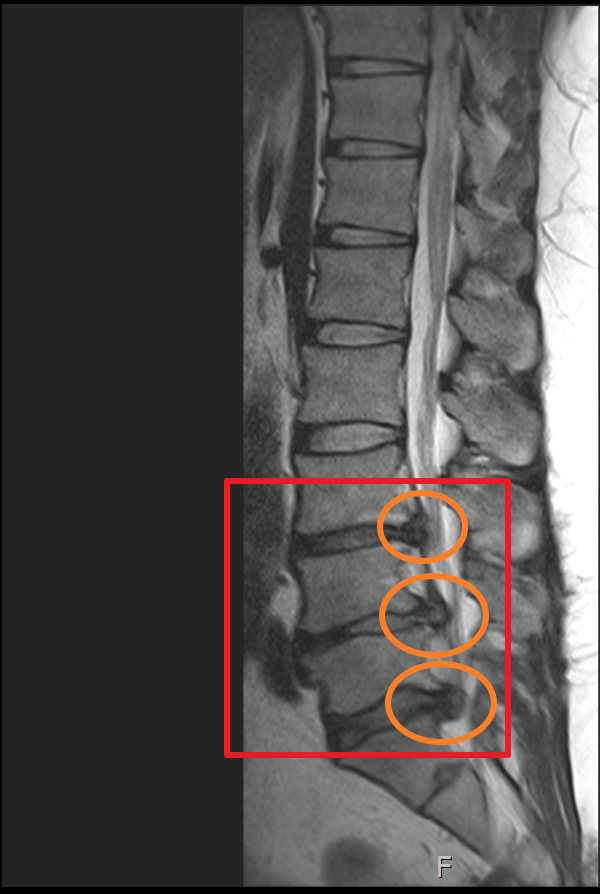

하지만 몸 관리를 꾸준히 잘하지 못하였고 4년 뒤 다시 허리디스크 상태가 악화하여 두 번째 MRI를 찍어보니 이전에 발병한 위치와 다른 곳에서 신경을 누르고 시작하였고 이전에 최초 발병한 허리디스크(첫 번째 동그라미)는 좀 나아졌으나 다른 곳에서(두 번째, 세 번째 동그라미) 또 문제가 생겼더군요.

마지막 허리디스크 MRI는 2020년에 촬영했습니다. 마찬가지로 사진을 보시면 최초 발병한 허리디스크 첫 번째 동그라미는 흡수가 된 게 눈에 보일 정도였으나 4년뒤엔 두 번째 동그라미와 세 번째 동그라미 디스크가 많이 튀어나와 신경을 누르고 있는 게 보입니다.

하지만 MRI 상 표시된 부분을 보면 첫 번째 허리디스크가 튀어나왔던 부분이 흡수된 게 확실히 보이며 이제는 다른 부분에 허리디스크가 눌려 신경을 누르고 있는 게 보입니다.

마지막으로 제가 촬영했었던 MRI 촬영 이미지를 첨부해 볼까 합니다. 이미지 순서대로 2014년, 2018년, 2020년 촬영했던 MRI 사진입니다. MRI 촬영 당시 허리디스크 상태가 좋지 않은 상황에서만 세 차례 찍었던 것이기에 이점도 고려해서 참고하시면 좋을 듯합니다.

이미지를 보시면 빨간색 네모 칸에 하얀색 기다란 세로 라인이 신경이 지나가는 부분이며 가장 바깥쪽 두꺼운 흰색 부분은 배 쪽의 지방입니다.

2014년 당시 대체로 튀어나온 허리디스크는 없으나 주황색 동그라미 부분에 엄청나게 많이 신경을 누르고 있었던 상황

2018년 첫번째 허리 디스크가 첫번째 디스크가 여전히 눌려져 있으며 추가로 두번쨰 디스크가 신경을 많이 누르고 있으며 세번째 디스크는 조금씩 나오는 상황.

2020년 첫번째, 두번째 터졌던 허리디스크가 많이 흡수되어 신경을 누르고 있는 디스크 압박이 많이 좋아졌으나 세번째 허리디스크가 터진 곳이 심해진 상황.